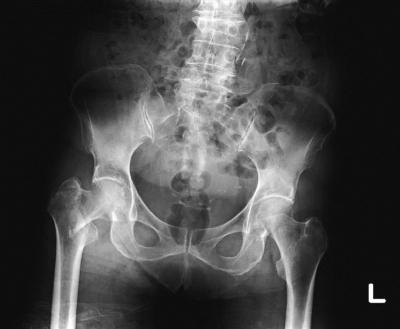

股関節エックス線写真を別に示す。最も考えられるのはどれか。

a. 恥骨骨折

b. 坐骨骨折

c. 腸骨骨折

d. 股関節脱臼

e. 大腿骨近位部骨折